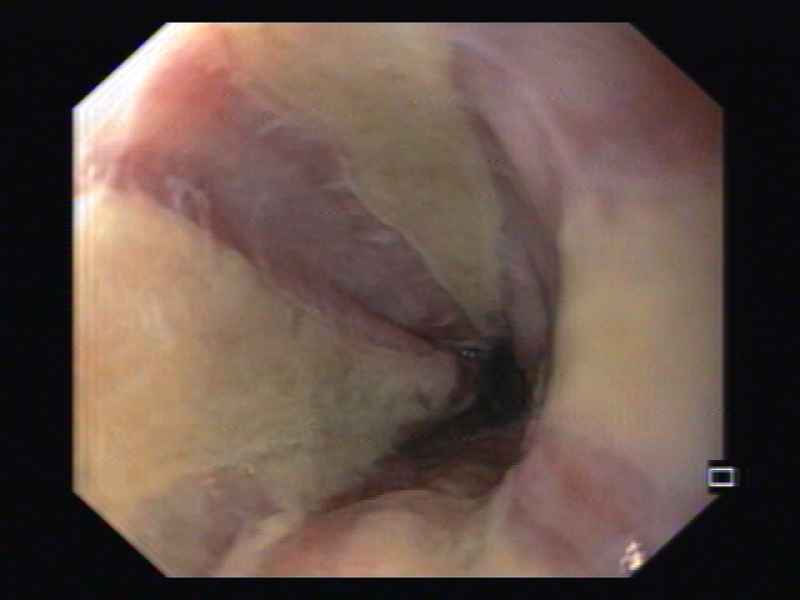

An unexpected esophageal finding: esophagitis dissecans

Fotografia